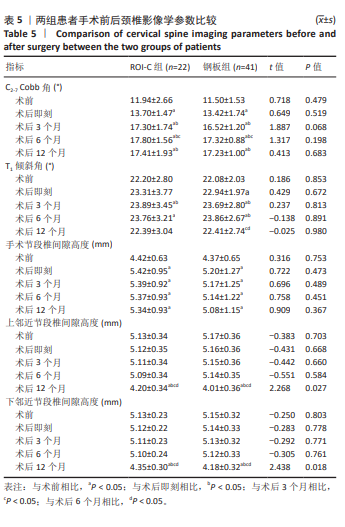

2.6 手术前后影像学评估 两组患者术后C2-7 Cobb角、T1倾斜角,椎间隙高度均较术前显著改善,两组组内不同时间点的C2-7 Cobb角、T1倾斜角,椎间隙高度比较存在显著差异(P < 0.001),而不同分组之间的评分差异无显著性意义(P > 0.05),并且两组在不同时间点的趋势也无显著差异(P > 0.05)。 ROI-C组术后即刻、术后3,6,12个月的C2-7 Cobb角、手术节段椎间隙高度及术后3,6个月的T1倾斜角较术前均显著增加;术后3,6,12个月的C2-7 Cobb角、术后3个月的T1倾斜角均较术后即刻明显增加;术后6个月的C2-7 Cobb角较术后3个月明显增加,差异有显著性意义(P < 0.05)。钢板组术后即刻、术后3,6,12个月的C2-7 Cobb角、手术节段椎间隙高度及术后即刻、术后3,6个月的T1倾斜角均较术前明显增加;与术后即刻相比,钢板组术后3,6,12个月的C2-7 Cobb角及术后3,6个月的T1倾斜角均明显增加;术后6个月的C2-7 Cobb角较术后3个月明显增加,术后12个月的T1倾斜角较术后3个月明显减小;术后12个月的T1倾斜角较术后6个月明显减小,差异有显著性意义(P < 0.05)。见表5。"

2.7 术后并发症评估 2.7.1 吞咽困难情况分析 在ROI-C组中,术后出现吞咽困难的病患数为4例,占该组总数的18%(4/22),此症状在术后3个月内自行缓解。相比之下,钢板组术后发生吞咽困难的患者较多,共计14例,发生率为34%(14/41);术后3个月时,钢板组内仍有7例(17%)患者持续存在吞咽困难;至术后6个月的随访时,这些患者的吞咽困难症状均得到显著改善或消失。统计结果显示,两组间在术后吞咽困难的发生率上未见显著性差异(χ2=1.788,P=0.181);ROI-C组术后3个月吞咽困难发生率显著低于钢板组(Fisher确切概率法P=0.041)。 2.7.2 邻近节段退变情况分析 ROI-C组与钢板组患者在术后3,6个月的时间点上,均未报告有邻近节段退变发生。术后12个月,ROI-C组中观察到邻近节段退变病例1例,占比5%(1/22);而钢板组内则出现3例邻近节段退变,占比7%(3/41),两组差异无显著性意义(χ2=0.029,P=0.866)。 两组术后12个月的上邻近节段和下邻近节段椎间隙高度均较术后即刻明显降低,但钢板组邻近椎间隙高度下降程度较ROI-C组明显增高,差异有显著性意义(P < 0.05)。两组间术前、术后即刻、术后3,6,12个月的C2-7 Cobb角、T1倾斜角、椎间隙高度相比差异均无显著性意义(P > 0.05)。 2.8 植入物与宿主的生物相容性 术后6个月时,ROI-C组出现1例未融合(5%),钢板组出现1例(2%);术后12个月时两组患者全部获得融合,两组间无明显差异(P < 0.05)。两组术后均未出现植入物周围感染、过敏反应、免疫反应及排斥反应。部分患者(ROI-C组3例、钢板组9例)术后出现体温轻度升高(小于38 ℃),在术后3 d内均得到恢复。术后各时间节点均未发现植入物破损、松动、脱落。 2.9 典型病例 影像学资料见图3,4。"